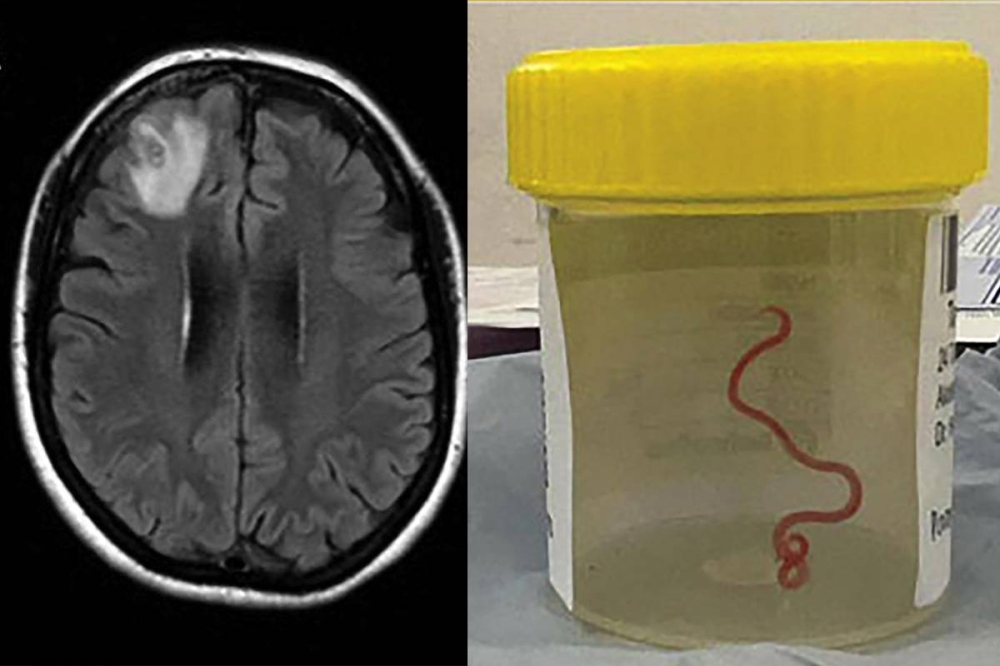

قدّم عالم أسترالي اليوم الثلاثاء تفاصيل اكتشاف هو الأول من نوعه في العالم بعد العثور على دودة طفيلية طولها ثمانية سنتيمترات داخل دماغ امرأة في كانبيرا مما يسلط الضوء على مخاطر انتقال الكائنات المعدية إلى البشر.

ويشيع وجود هذه الدودة، التي يصنفها العلماء بأنها مستديرة، داخل نوع معين من الأفاعي، وعثُر عليها العام الماضي في دماغ امرأة تبلغ من العمر 64 عاماً بينما كانت تجري عملية جراحية في العاصمة الأسترالية بعد شكاوى من آلام في البطن والنسيان والاكتئاب.

وتُشير دراسة عن الحالة نشرت أمس الإثنين في دورية الأمراض المعدية الناشئة إلى أن المرأة ربما التقطت الدودة وهي تبحث عن أعشاب برية ربما كانت ملوثة بفضلات الأفاعي.